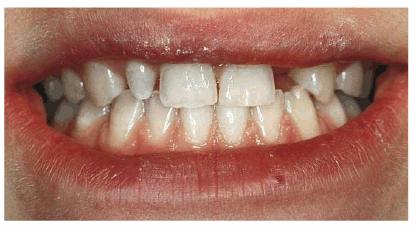

A male patient, 2 years and 8 months old, with interproximal caries of D, E, F,

and G (Figures 27-1A

and B

Figure 27-1A and B: Interproximal caries of frontal anterior teeth are removed, and a morphic-functional composite restoration is performed.

PROBLEM: The patient was not compliant, but an initial radiographic

examination was accomplished.

TREATMENT: Under conscious sedation, in only one visit, caries lesions

are removed, and the morphic-functional restoration with composite resin is

placed.

RESULT: The restoration achieved the esthetic goal and restored function

and anatomy. Furthermore, in a situation of tooth crowding, the arch length was

preserved. Both the patient and his parents were pleased.